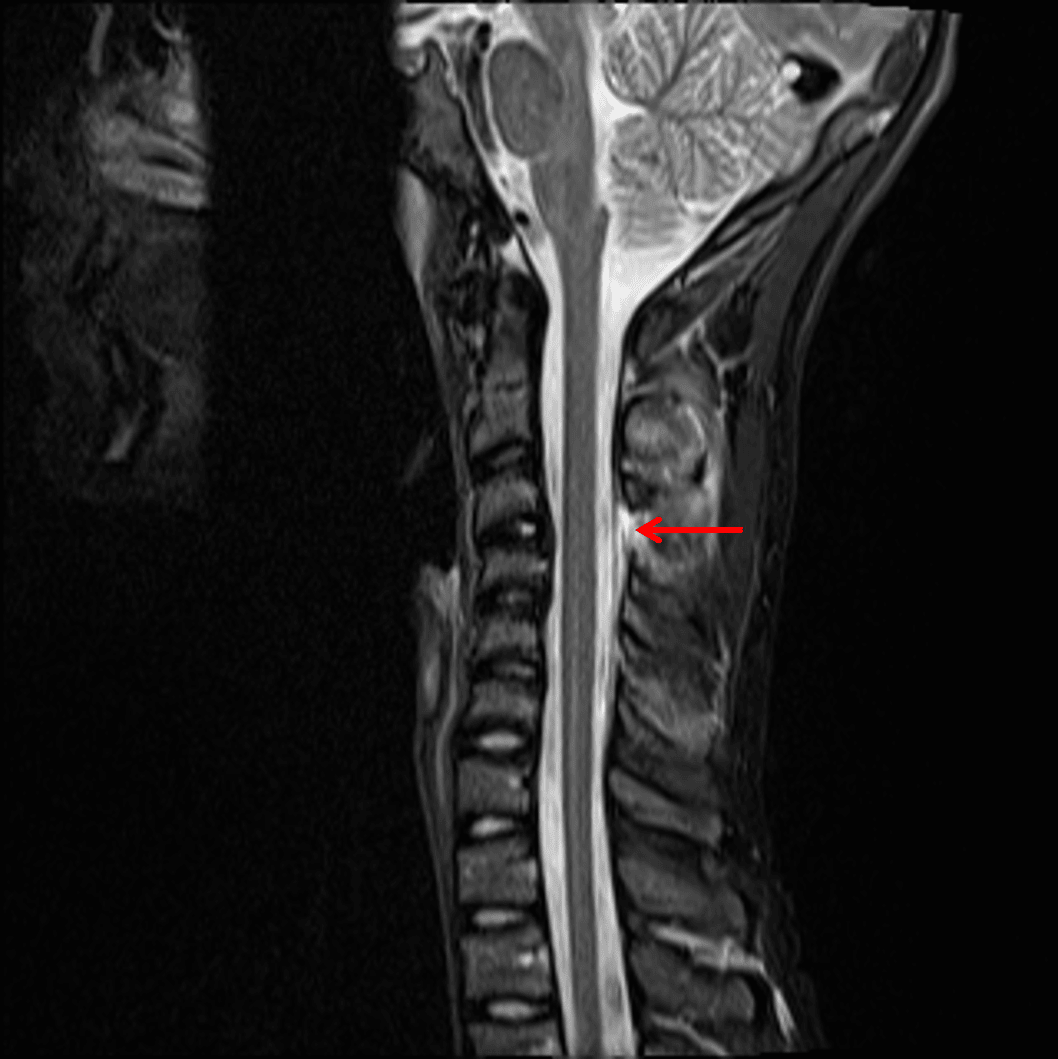

- Focal kyphosis with widening of the interspinous interval at C3-C4

- Perched right C3-C4 facet joint

- T2/STIR hyperintensity in the interspinous ligaments at multiple levels, most pronounced at C2-C3, C3-C4, and C5-C6, and in the supraspinous ligament at the levels of C2-C3 and C3-C4

- T2/STIR hyperintensity in the right C3-C4 facet joint

- Focal discontinuity of the ligamentum flavum at the level of C3-C4 and possibly at C5-C6

- Small posterior disc bulges at C3-C4 and C4-C5 result in partial effacement of the ventral CSF without significant spinal canal stenosis

Flexion distraction injury at C3-C4 with traumatic kyphosis, widening of the interspinous distance, and perched right C3-C4 facet. No marrow edema to suggest acute fracture, though CT should be considered for further evaluation given that only radiographs were obtained previously.

Findings concerning for focal disruption of the ligamentum flavum at C3-C4 and possibly at C5-C6, right C3-C4 facet capsular injury, multilevel interspinous ligament injury, most pronounced at C2-C3, C3-C4, and C5-C6, and supraspinous ligament injury at C2-C3 and C3-C4.

Likely traumatic disc bulges at C3-C4 and C4-C5, which partially efface the ventral CSF without significant spinal canal stenosis.

- Hyperflexion injuries result in narrowing of the anterior column and widening of the posterior column, as shown in this case with kyphotic deformity and widening of the interspinous distance at the involved level

Cervical Ligamentous Injury 1.1